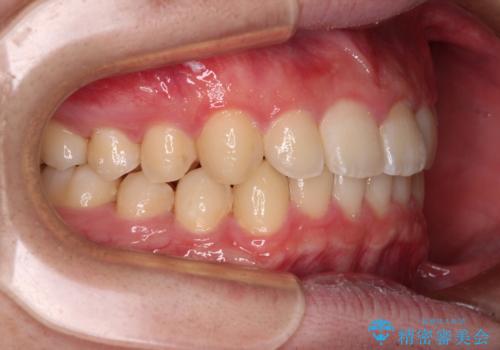

- 前方に傾斜した前歯を気にして来院された患者様です。

強く食いしばってしまう癖があり、下顎前歯に押し出されて上顎前歯が前方へ斜めに突き出している状態でした。

IPR(歯と歯の間を削る)を多用して、インビザラインにて矯正治療を行うこととしました。

口元を引っ込めるためのゴムかけを頑張っていただき、満足のいく上顎前歯の傾斜へ改善することができました。